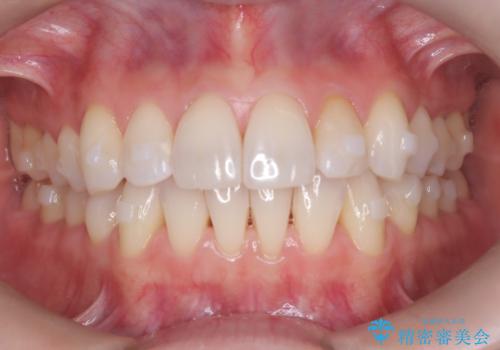

矯正後の後戻りで前歯にガタツキができてしまった インビザラインで改善

- 子どものときにワイヤー矯正をしていたが、後戻りによって前歯のガタツキが気になってきたとのことで来院されました。

アライナー矯正希望だったため、インビザラインによる治療を行いました。